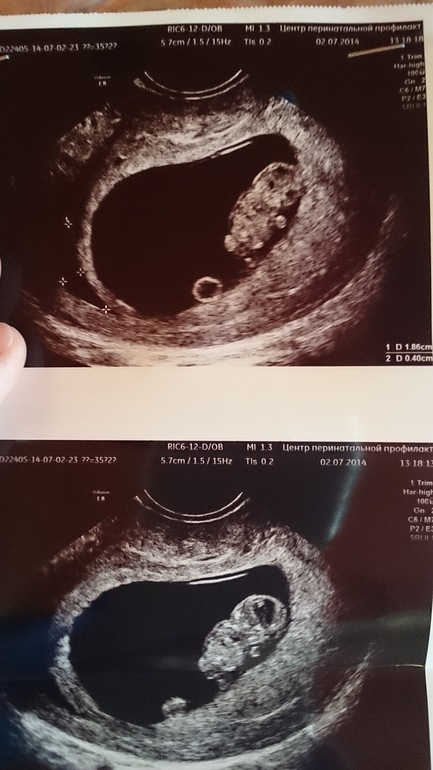

Наша малявка и киста

ОРВИ, грипп, простуда, заболевания во время беременностиВсем привет! Вот мы уже на 10 недельке, на прошлой неделе делали узи. Все ок, но есть киста. У кого было? Прокомментируйте, пожалуйста.